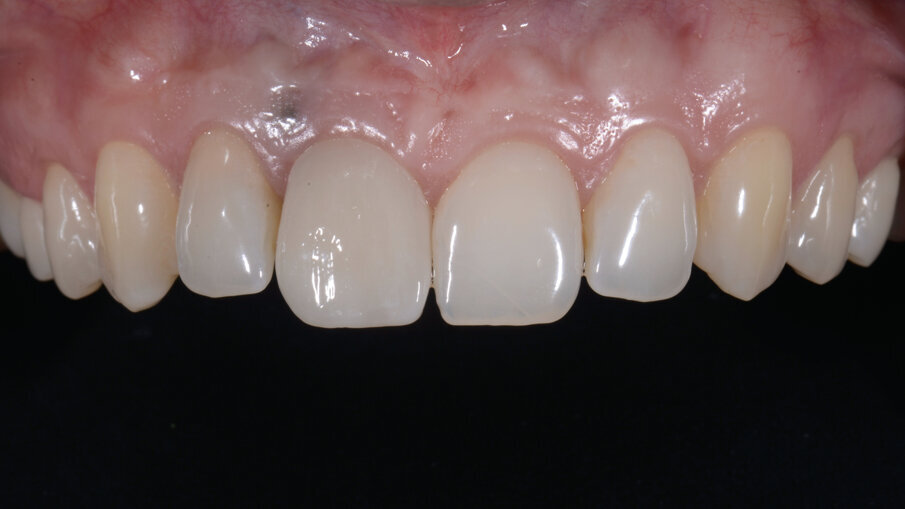

- Fresatura del dente protesico e sua finalizzazione

Il dente progettato è stato fresato utilizzando un cubetto di disilicato di litio forato e a bassa translucenza per meglio mascherare il grigiore del titanio del Tbase. Dopo avere scolpito la tessitura superficiale, il dente è stato lucidato utilizzando gomme con diverso grado di abrasività al fine di diversificare le diverse aree del dente rendendolo più naturale e in armonia con i denti vicini (Figg. 33-35). In corrispondenza della gengiva aderente è evidente un tatuaggio relativo alla posizione della pregressa fistola che potrà essere eliminato in qualsiasi momento qualora la paziente lo richiedesse. Le immagini ad 1 anno mostrano la stabilità nel tempo dell’ottimo risultato ottenuto (Figg. 36, 37).

Fig. 33_Prova delle forme e verifica del grado di compressione dei tessuti molli vestibolari.

Fig. 34_Dente protesico definitivo dopo le opportune fasi di finalizzazione.